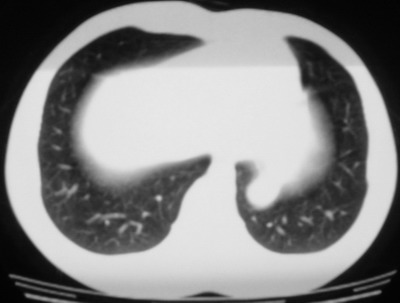

以下是引用余辉在2007-6-16 20:47:00的发言:[br]图像不边续,1左肺下叶膈后囊性病灶,与胃有密切联系,考虑局限性膈膨隆,不排除其他如脓肿等;2左膈肌脚增厚,其前方肝胃间隙内可见球形病灶,左肾上腺病变?进一步检查

以下是引用xulianj在2007-6-16 21:14:00的发言:[br]左膈肌脚增厚,支持膈肌角病变。

以下是引用卜一在2007-6-17 4:50:00的发言:[br]左膈肌脚增厚,支持膈肌角病变。